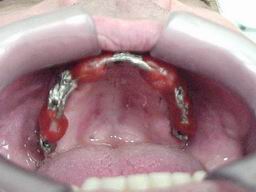

Fases laboratoriais para confecção da barra fundida da "Protocolo" superior:

Réplicas dos componentes sobre implantes (modelo de gesso) Enceramento da barra superior sobre as réplicas no modelo de gesso

Vistas laterais do enceramento

Prova da estrutura fundida, seccionamento e preparação para solda Barra soldada com dentes montados em cera para prova de articulação

Vista oclusal da "Protocolo" antes da acrilização Superior: Prova de montagem em cera      sobre barra fundida.